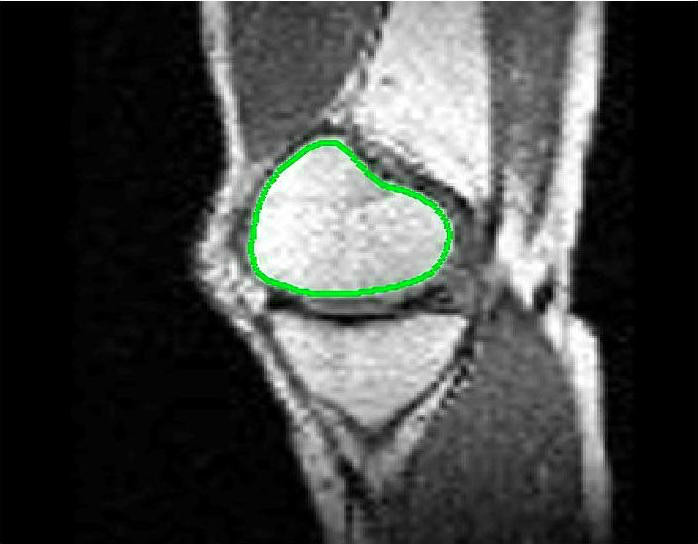

The motivation for this work comes from observing contradictions in using piecewise-constant intensity fitting terms in selective segmentation. Whilst good results are possible with this approach, the exceptional cases lead to severe limitations in practice. This is quite common in medical imaging as demonstrated in Fig. 1, where the target foreground has a low intensity. Given that the corresponding background includes large regions of low intensity, the optimal average intensities for this segmentation problem are and . For cases where , we see that by (1), almost everywhere in the domain . This means that it is very difficult to achieve an adequate result, without an over-reliance on the user input or parameter selection.

Test Images. We will perform initial tests on the images shown in Figs. 5–7. We have provided the ground truth and initialisation used for each image. Test Images 1–3 are synthetic, Test Image 4 is an MRI scan of a knee, Test Images 5–6 are abdominal CT scans, and Test Images 7–9 are lung CT scans. They have been selected to present challenges relevant to the discussion in §2. We focus on medical images as this is the application of most interest to our work. In the following we will discuss the results in terms of synthetic images (1–3) and real images (4–9). We also test the proposed approach on a larger data set of 30 CT images (a sample of which is presented in Fig. 18), comparing against existing selective methods detailed in §3.